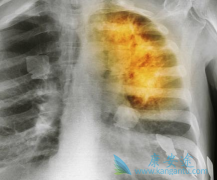

• 肺癌晚期还有救吗?如何治疗肺癌晚期

肺癌晚期还有救吗?如何治疗肺癌晚期

一般来说肺癌患者只要被确诊为晚期,患者和家属就会很迫切的想知道,治疗情况如何?晚期有救吗?虽然说癌症目前还不能达到完全治愈的目的,但仍有不少晚期肺癌患者带瘤生存,治疗效果不错,生活质量也很高的案例。肿瘤不止手术切除、放化疗、中医治疗等 ...

• 肺癌晚期可以治好吗是患者非常关注的问题

肺癌晚期可以治好吗是患者非常关注的问题

患者得了肺癌,能活多久是大家关心的问题,很多人都希望肺癌能够治好,但是大部分人觉得肺癌晚期基本上治疗无望,只能等待死亡。很多患者在肺癌晚期时来咨询康安途海外医疗,本身在医生的建议下打算治疗的,寻求二次建议。那么 肺癌晚期可以治好吗 ?   ...

• 肺癌晚期可以治好吗?吉非替尼如何治疗肺癌

肺癌晚期可以治好吗?吉非替尼如何治疗肺癌

到了肺癌晚期,大部分人觉得最好的方法是手术,其实这不是绝对的,对于晚期肺癌,癌症已经扩散到身体的很多地方,不建议采取手术治疗。众多治疗方法中,采用药物的手法来治疗肺癌是最有效并且毒副作用是很小的,可以有效的抑制癌细胞的扩散,还可以缓解 ...

• 肺癌晚期可以治好吗?如何治疗肺癌晚期

肺癌晚期可以治好吗?如何治疗肺癌晚期

肺癌有很多种,比如有肺癌腺癌、小细胞肺癌、支气管肺癌等。而且肺癌一旦发展至晚期,疾病的治愈率较低,那么 肺癌晚期可以治好吗 ?肺癌晚期患者,癌细胞已经通过血液循环或者淋巴系统转移至身体的各个部位,疾病的恶性程度较高。患者随时都面临着生命 ...

• 肺癌晚期能治吗?靶向治疗肺癌疗效如何

肺癌晚期能治吗?靶向治疗肺癌疗效如何

早期肺癌比较好治疗,手术经常是第一方案,患者五年生存率可达80%-90%。通常到了肺癌晚期,手术治疗的难度非常大,综合患者的体质、病情状况也无法接受手术治疗,而且 肺癌晚期 易发生转移或者扩散的情况。   所以,止痛、控制病情、更好的活着、活得 ...

• 肺癌晚期能治吗?治疗肺癌主要方法有哪些

肺癌晚期能治吗?治疗肺癌主要方法有哪些

总所周知肺癌是非常难以治愈的,特别是到了肺癌晚期的时候。病人的身体状态都不是特别好,治疗的难度也非常大。那么, 肺癌晚期能治吗 ?要怎么治疗呢?接下来。大家就跟小编一起来看看吧。   肺癌晚期怎么治疗:化学治疗,这些年来,肺癌的化疗很受关 ...